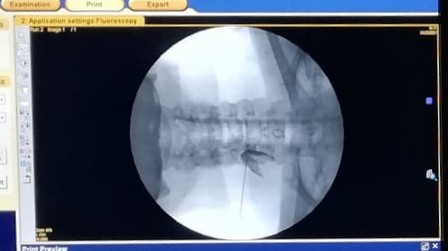

This is the needle going into the foramen to bathe the nerve root in local anaesthetic and corticosteroids. The dark stuff is dye.

The doctor and specialist nurse who did the procedure were fantastic: everything was explained in detail, my own level of knowledge was accepted instead of seen as Internet-overuse so we could discuss things on a sufficiently clinical level, and although the procedure itself was very painful, extremely weird, and left me feeling the next day like I'd been hit by a high-speed bicycle courier, I could tell that it was being done with extreme care, attention, and professionality, which even while it was happening alleviated any fears I might have had regarding some of the more common side effects (for example, a few days of extreme muscle stiffness and headache because of the delivery of a bolus of medication to the area). Also while it was happening, I became aware that I was not going to become the unlucky one in 3,700 who develops temporary (4 to 10 months) quadriplegia (this statistic being of course world-wide-based and covering all hospitals and all doctors on the planet, good or bad, so I wasn't all that worried because of where I found myself undergoing this). That happens immediately, if it's going to. Overall, 0 out of 10 for having to go through something like this in the first place but a big 10 out of 10 for getting it done there, by these people.